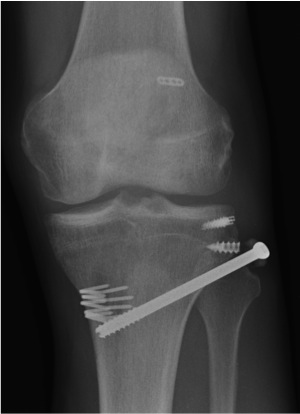

Acute fixation of bony avulsion of fibula with screw

- screw fixation of bony fibular avulsion into tibia if piece large enough